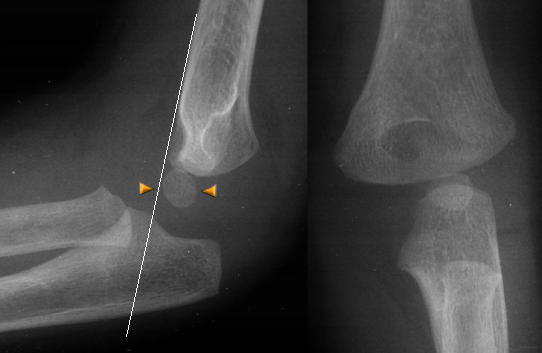

Se efter intra artikulær ansamling (prøv at stille på

kontrasten så bliver det tydligere):

:

Husk at vurdere at caput radii er på plads, ved at

kontrollere at en linje gennem radius går gennem centrum af capitulum humeri:

Undersiden af ulna skal være helt lige:

Ved en bowing ulna ses ofte caput radii luksation: